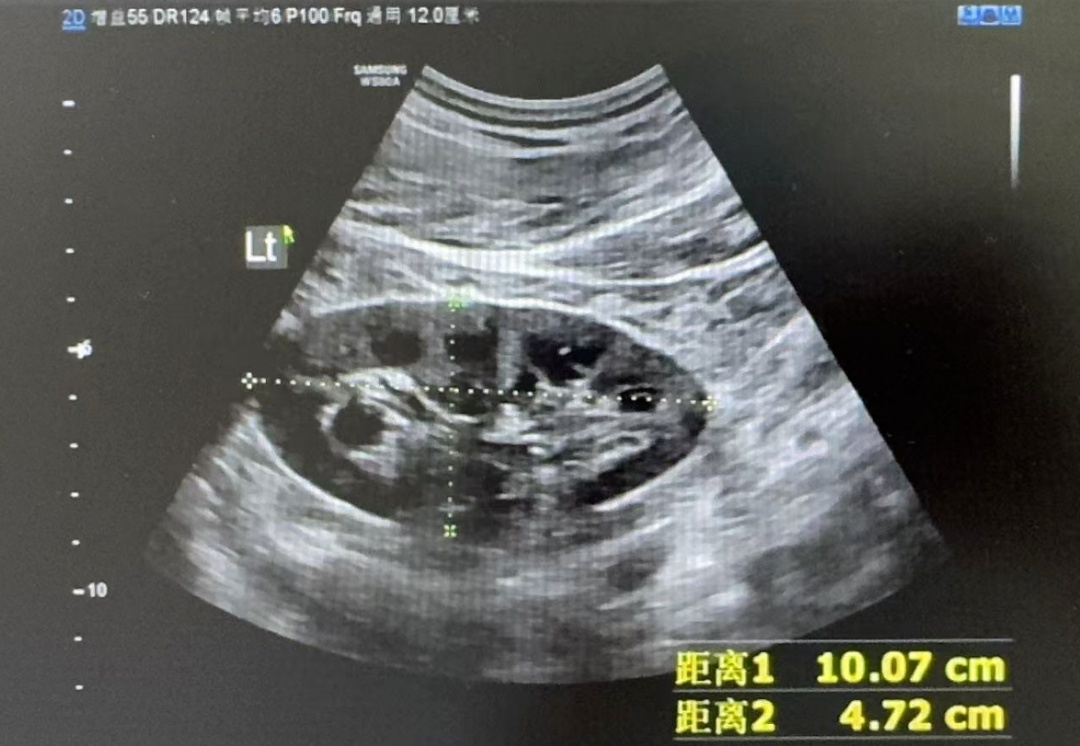

冯先生辗转来到深圳市某医院肾内科,接受了肾脏超声检查。

结果显示,冯先生的双肾并没有萎缩,结构完好,这表明不存在慢性肾病基础,而是急性肾功能衰竭。